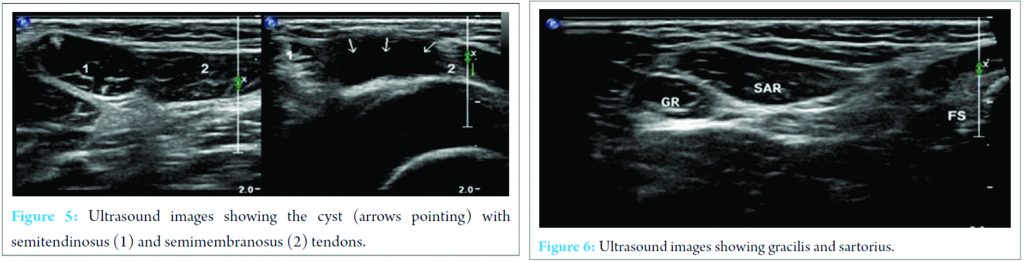

X-ray of the knee joint was unremarkable (Fig. 3, 4). Ultrasonography (USG) revealed a hypoechoic well-defined cystic lesion with clear contents is visualized on the antero-medial aspect of the left knee over the semitendinosus tendon. The lesion measures 25 mm × 10 mm. The lesion is causing splaying of the gracilis and sartorius muscles near knee; the lesion extends lower down and posteriorly and appears to fuse close to pes anserine insertion near the pulsation of the medial geniculate artery (Fig. 5, 6). Doppler USG showed no evidence of vascular involvement.